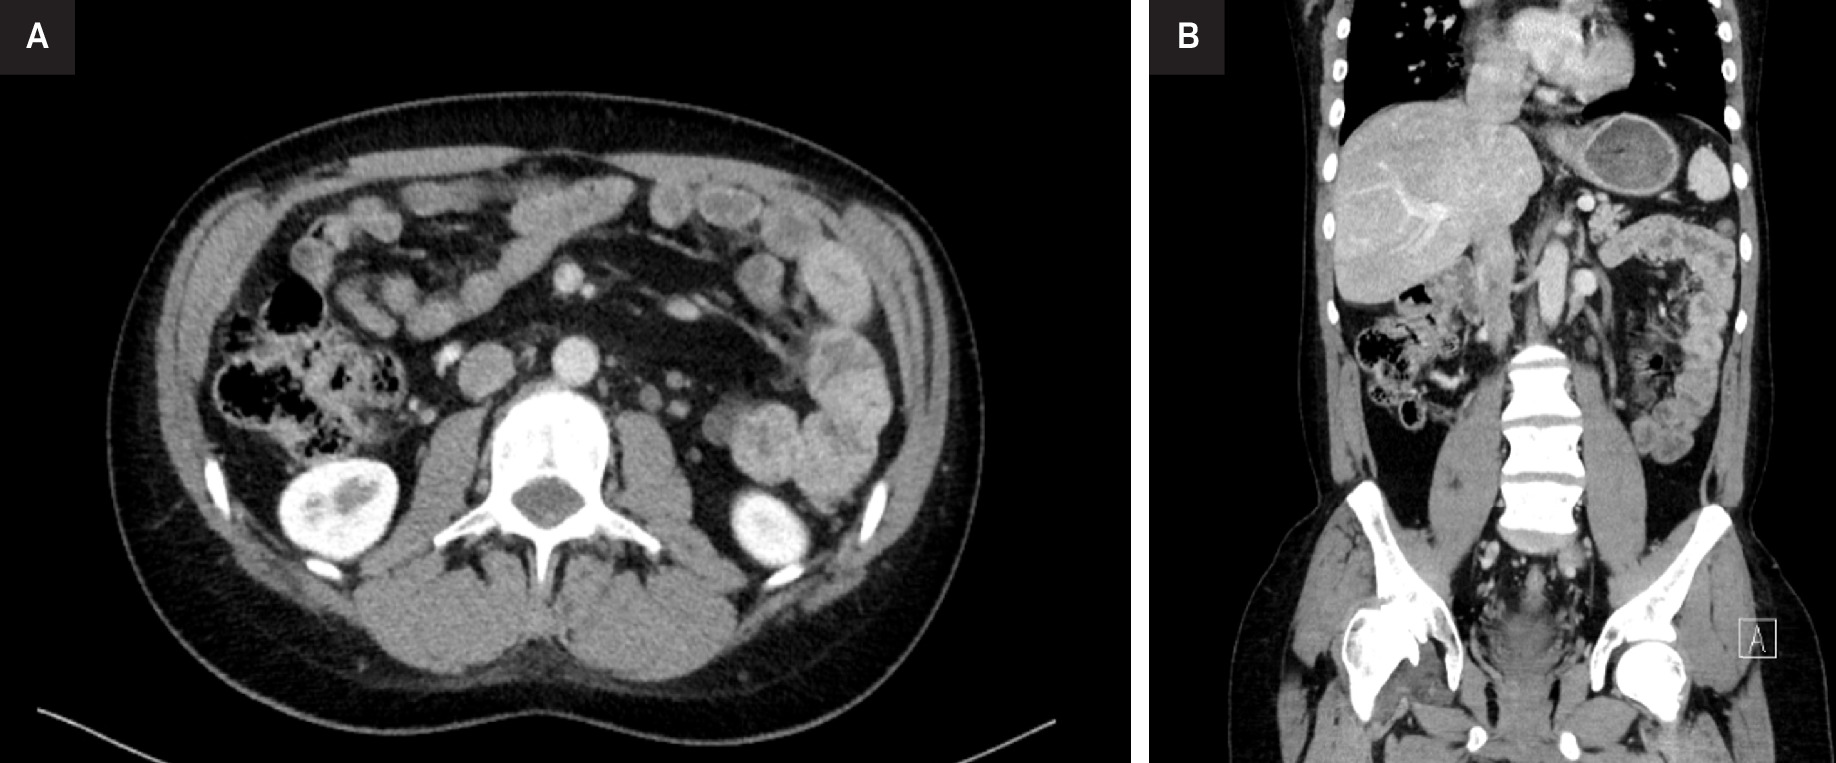

The patient tolerated treatment well, experiencing only mild nausea, with no other documented symptoms. A reassessment CT-TAP scan after 3 months revealed a reduction in left lateral aortic adenopathy to 13 × 10 mm, with the disappearance of the remaining metastatic lymph nodes.

Since undergoing RT, the patient has remained in good health, asymptomatic, and free of treatment-related toxicities. Follow-up imaging at 1 year revealed a complete response (CR) regarding the left lateroaortic adenopathy according to RECIST criteria (Figure 3). 23 The patient remains stable at 12-month follow-up.